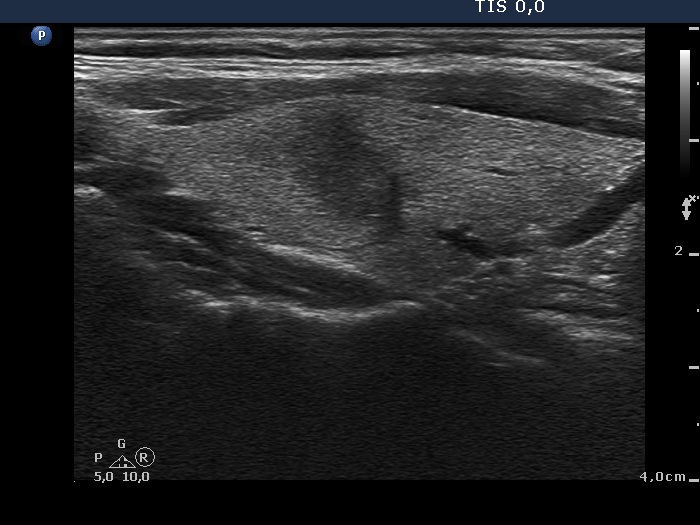

Follow-up 6 months after the first visit (3rd row of images):

Clinical presentation: The patient had no complaints.

Palpation: no abnormality.

Laboratory tests: TSH 2.06 mIU/L, FT4 13.3 pM/L, CRP 0.3 mg/L.

Ultrasonography: The pattern of the entire thyroid became almost completely normal. Only small hypoechoic areas were observed.

Suggestion: TSH in six months, in the event of pregnancy at once.

Follow-up 5 years later (3rd row of images):

Clinical presentation: Six months after the previous visit the patient became pregnant. The TSH was 5.91 mIU/L at the 5th gestational weeks. Replacement therapy was given which was ceased after delivery. The patient was free of complaints and the TSH was in the normal range, even during a next pregnancy 2 years later. Recently, a few weeks after COVID-19 infection, she noticed tenderness in the right side of the neck.

Laboratory tests: TSH 1.72 mIU/L, CRP 3.5 mg/L.

Ultrasonography: The thyroid was intact.